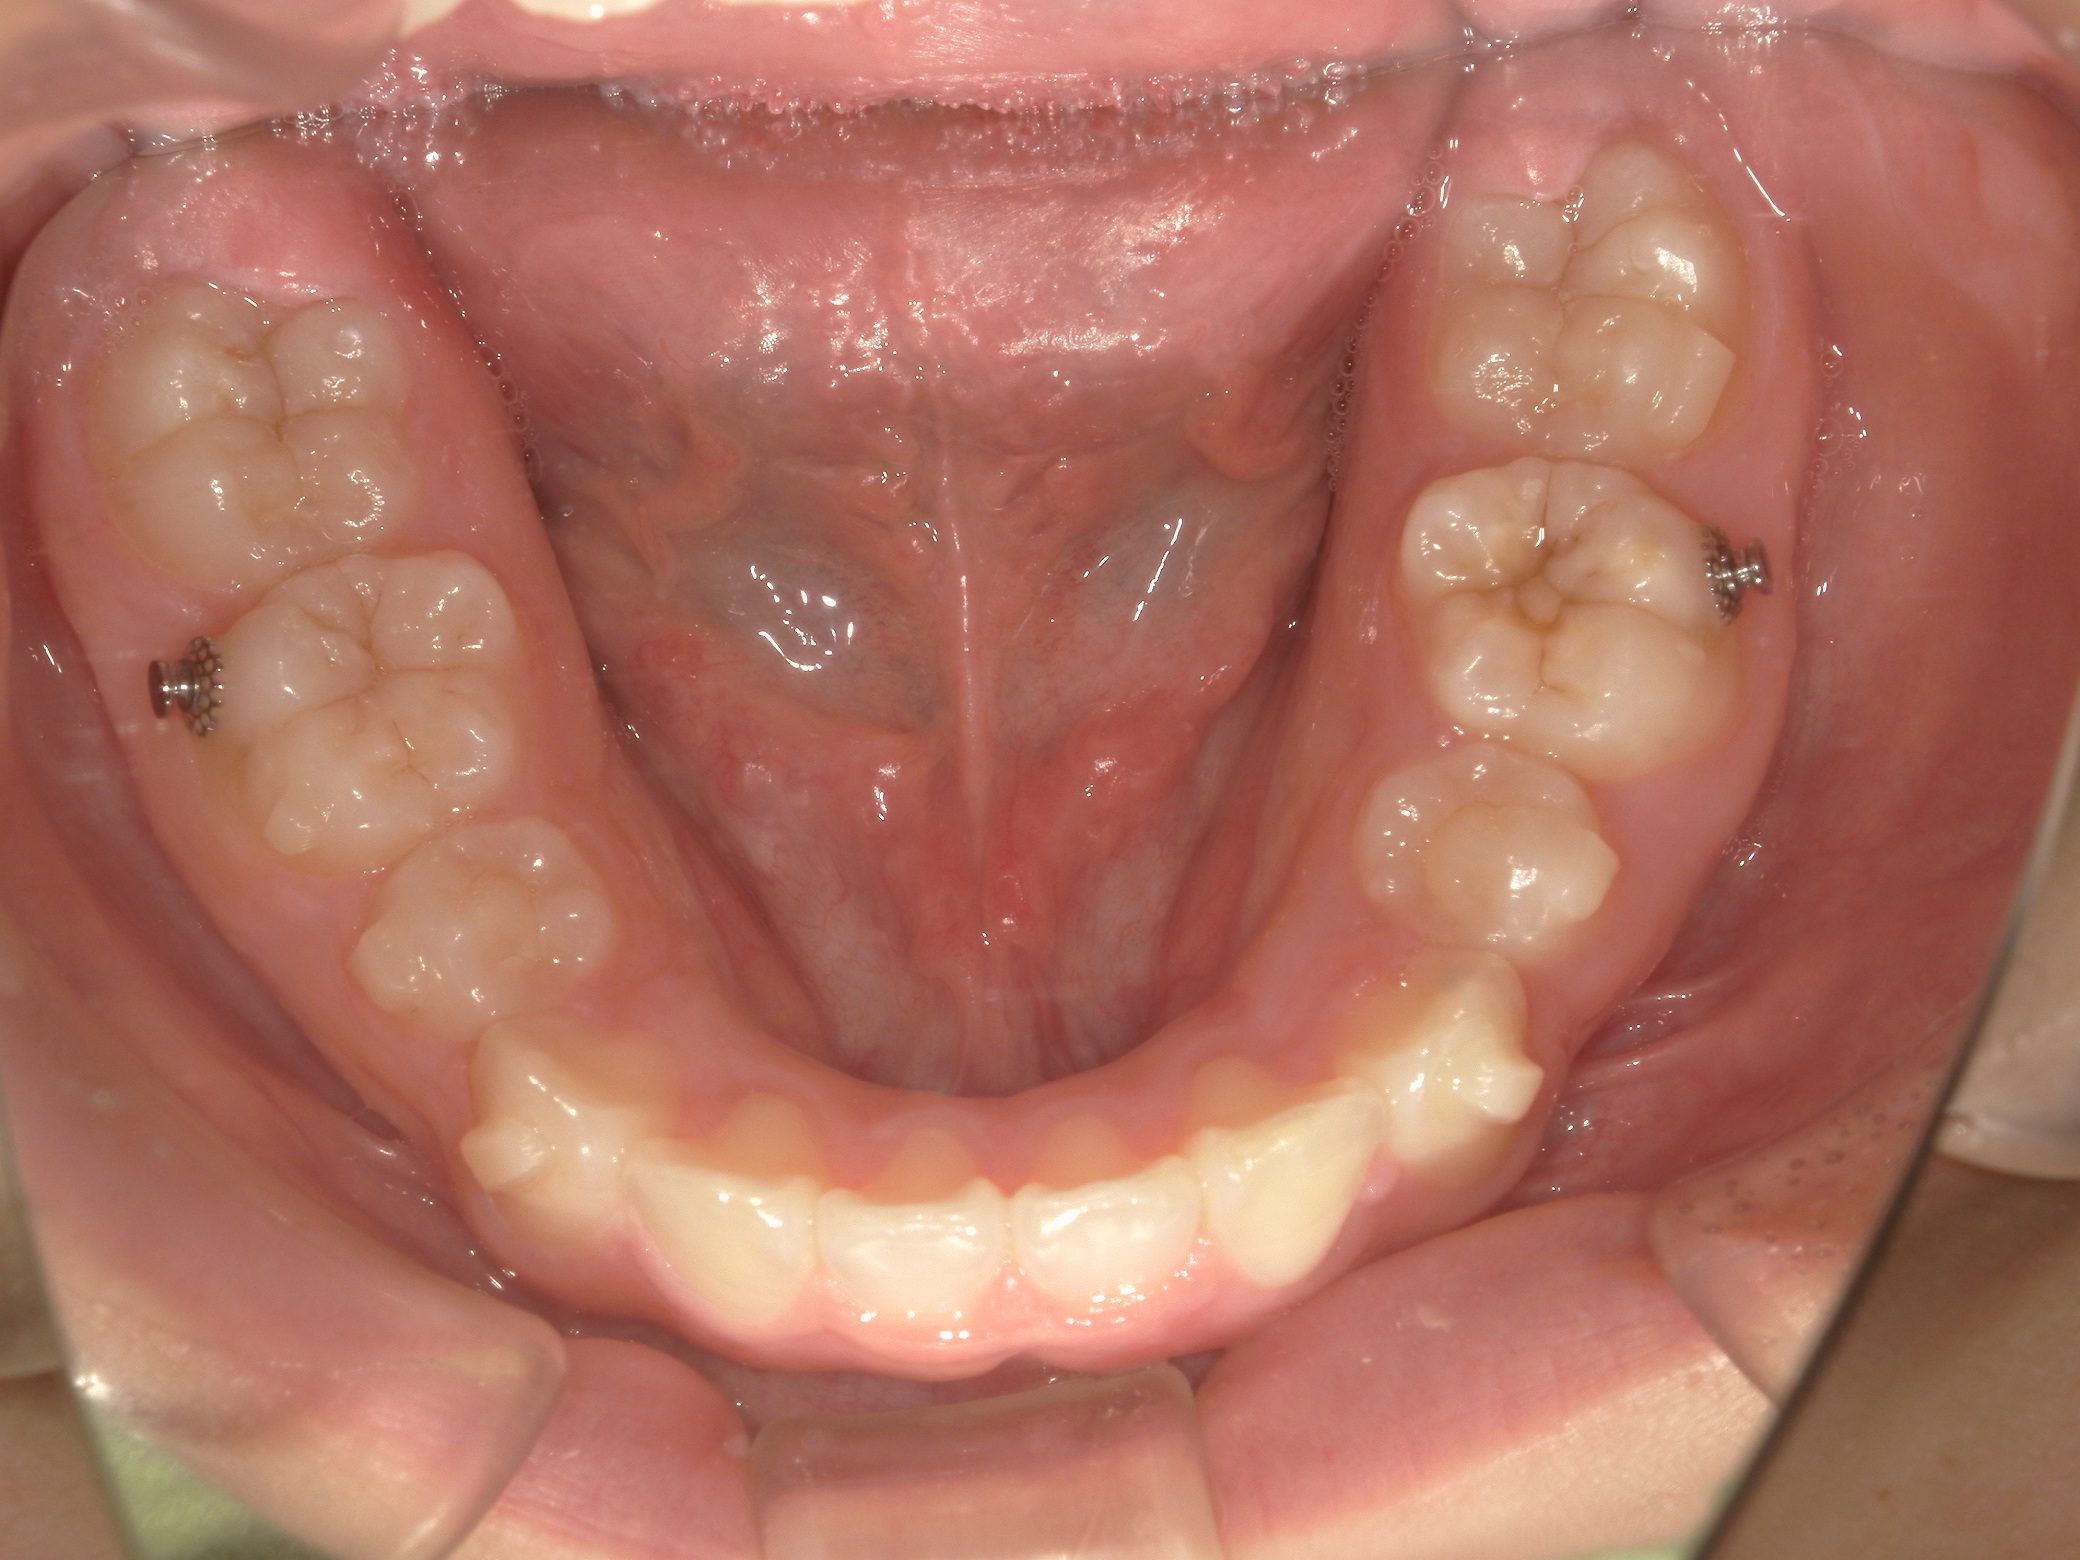

【小学生】インビザラインフル 叢生(でこぼこ)と 上顎前突(出っ歯)を改善

Before

After

八重歯と上顎前突(出っ歯傾向)が気になるということで来院

上下4本の歯を抜歯して矯正しました

しっかり装着してくれたので3年はかかると予測していましたが、1年半で終了しました

咬み合わせも改善し満足してくれました